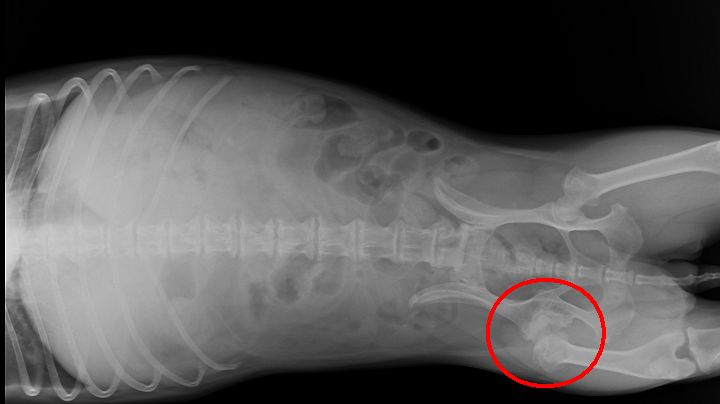

"你看看, 小黃的脊椎, 每一骨節都有增生物, 這就是骨刺. 而且二節骨刺還連起來變骨橋... "

"而這邊, 蠻嚴重的, 偏偏就是脊椎神經出來控制膀胱的地方."

"所以覺得有可能是這裡的神經受壓迫, 而誤下了收縮尿道憋尿的指令. "

(藍圈是一般的骨刺, 綠圈是骨刺搭成骨橋, 紅圈是這次事件的嫌犯)